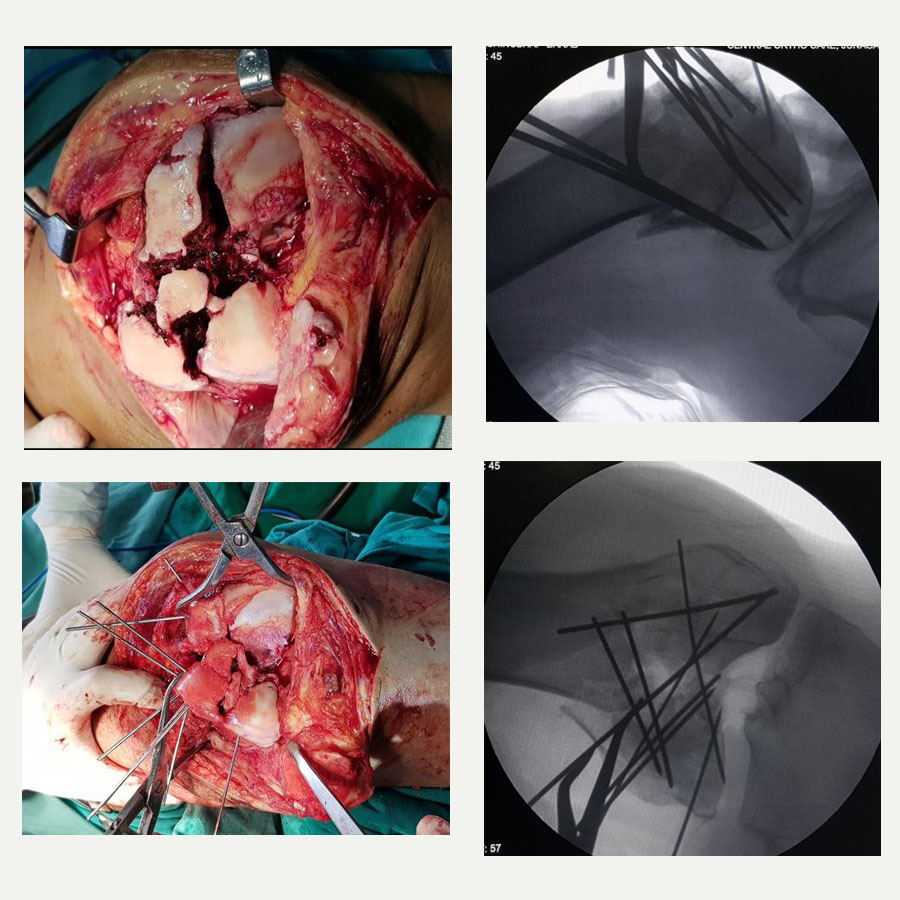

The joint was exposed via an open procedure similar to that used in total knee arthroplasty, allowing us full visibility. What we encountered were multiple fragments, many of which were too small to individually identify without proper sequencing – much like solving a jigsaw puzzle. The first step was to reconstruct the articular surface using temporary fixation with Kirschner wires (K-wires). Fragment by fragment, we identified and aligned them to reform the joint’s surface. Once reconstructed, this block of bone was then aligned with the diaphysis of the tibia.

One of the critical intraoperative challenges was the presence of a void within the area, a consequence of both osteoporosis and the impact of the fall. Anticipating this, we had prepared to perform bone grafting. Autologous bone was harvested from the patient’s iliac crest and packed into the cavity to provide structural support and facilitate fracture healing.

Permanent fixation was then achieved using two plates and multiple screws. Due to the unavailability of a dedicated plate for this particular fracture configuration, we used a shoulder locking plate, which fitted anatomically well for medial and lateral support. This unorthodox but carefully considered decision underscores the importance of improvisation when conventional tools fall short.